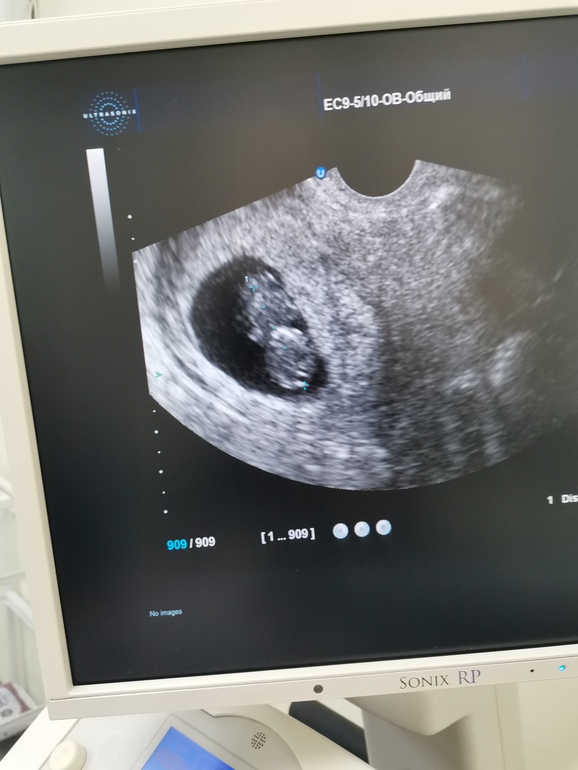

Врач сказал, что по узи все хорошо. Разрешила сфоткать экран. Потом разглядывала фото и поняла, что носа, да и вообще профиль я не вижу. В описании указано,Продолжение истории. Сходила к врачу, переделал он мне узи. Сказал, что это погрешность аппаратов и беременность протекает нормально,сказал не искать проблемы там, где её нет. В итоге по узи вчера пя 39*28, сегодня написал диаметр 45мм.но когда он мерил, сказал, что размеры зависят от положения датчика. И действительно, он крутит им и яйцо то вы

16. 02 делала узи, ПЯ - 14мм, КТР - 2ММ, Желточный мешочек 3мм, СБ +. Это был примерно 25 Дпо.

Сегодня пошла на узи, акушерский срок - 5 недель, 5 дней. Овуляция была примерно 22 января.

Плодное яйцо - 14мм

КТР - 2мм

С/б визуализируется